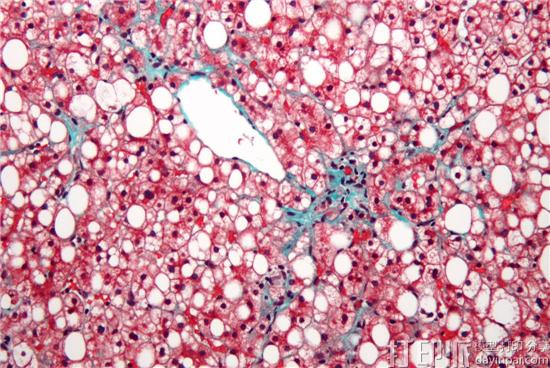

NAFLD与炎症和肝脏脂肪组织的超量有关,NASH则被认为是肝移植的第二大主要原因。它们均可能导致非常严重的疾病,如以肝硬化或肝癌。但通过这次合作,Organovo和Viscient有望找到治疗方法。